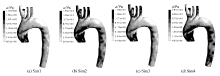

图4为 t=0.1 s时Sim1—Sim4的壁面切应力分布轮廓图。可以看出, Sim2和Sim3在左右锁骨下动脉和颈左右总动脉处的壁面切应力较大, Sim4降主动脉段和左锁骨下动脉壁面切应力值较大。这有可能是因为Sim2和Sim3在0.1 s时刻在左右锁骨下动脉的血流流量较大,而Sim4在降主动脉和左锁骨下动脉处的血流流量较大。